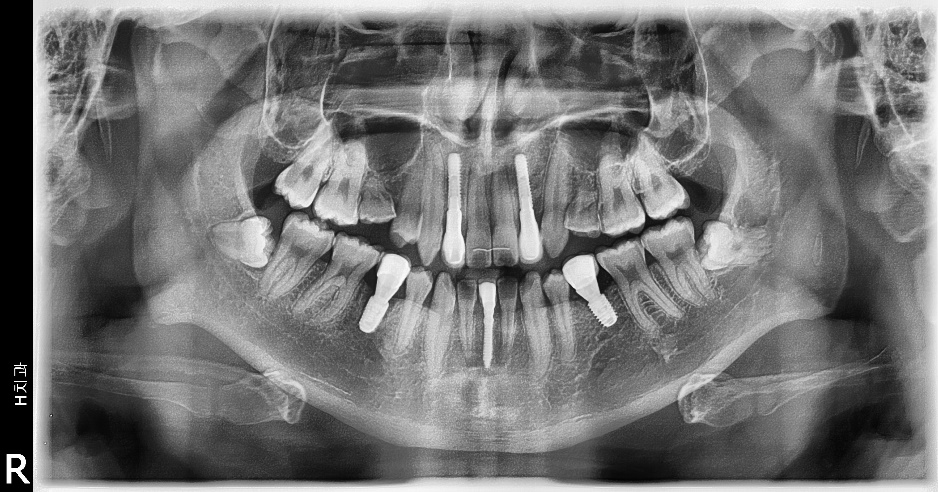

충분한 양의 측절치 공간 확보후 임플란트 식립및 보철로 치료를 마무리하였습니 다. 치근이동이 원활히됨으로 인해 임플란트 식립하기 충분한 공간이 확보되었으며 중절치의 전방이동으로 반대교합이 해소되었습니다.

일반적인 상악 측절치의 경우 전후방적 공간은 평균 6.5미리로 적정 임플란트의 직 경은 3.5미리가 적절하지만 위 증례의 경우 7.5미리를 교정원장님께서 확보해 주셨기 때문에 사용한 임플란트의 직경은 4.0미리를 사용하였습니다.

물론 그에 따른 순측골의 두께가 얇아질 수 있기 때문에 limited flap(Hincision)을 통 한 GBR(xenograft+resorbable membrane)을 시행하였습니다.

임플란트 보철치료가 완료된 후 생길 수 있는 잔여접촉점 사이의 공간 폐쇄를 위해 다시 교정의에게 의뢰하였습니다. 선천적 결손 부위인 하악 양측 제2소구치의 경우 하방의 골밀도는 일반적으로 떨어져 있는 경우가 많습니다.

초기 2.0/2.1/2.2의 드릴링 시에 골밀도를 정확히 체크하여 optimal underdrilling을 고려해야만 예지성있는 초기고정을 얻어낼 수 있고 또한 하방의 이공(mental foramen) 위치를 인지하며 수술을 해야 합니다.

하악전치의 경우 전후방적 공간은 5 미리내 외이므로 onebody implant, 필자는 이번 경우 덴티스의 I fix 2.5X13mm를 사용하였고 큰 무리 없이 임플란트 보철까지 완료하였습니다.